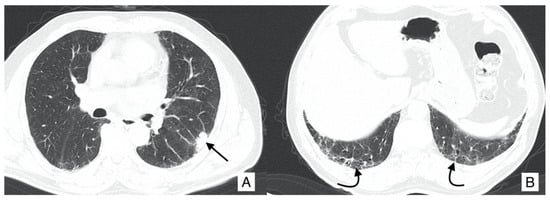

4.4. Pneumothorax

4.5. Pulmonary Infection